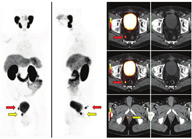

第二,CTVs可以被扩展到包括目前一线影像学未见的疾病区域,并且通常不是一致的CTVs靶点(图3)。第三,转移性疾病的证据表明,单靠局部治疗是无法治愈的。在寡转移性疾病(较低的转移性疾病负荷,在3~5处部位出现不同表达)的背景下,许多医师提供转移导向治疗,旨在局部消融转移灶(图4,图5,图6),转移导向治疗是当前众多临床试验的主题[54]。最后,在某些PET/CT意外显示的弥漫性转移病灶的病例中,放疗可能是无效的。

Souvatzoglou等[63]对37例前列腺癌根治性切除术后生化复发(中位PSA 0.5 μg/L)患者进行了回顾性研究,这些患者接受了11C-胆碱PET/CT检查。30%的患者11C-胆碱PET/CT阳性,其中盆腔淋巴结复发5例,前列腺床区内复发6例。患者最初均计划单独在前列腺床区行SRT,11C-胆碱PET显示有13.5%的患者盆腔淋巴结阳性。Würschmidt等[64]同样报道了18例生化复发患者(中位PSA 1.9 μg/L)行18F-胆碱PET/CT检查,患者最初均计划直接在前列腺床区进行SRT,87.5%的患者18F-胆碱PET/CT阳性,除1例外,余均因剂量增加或纳入盆腔淋巴结而影响了SRT。Ceci等[65]报道在95例前列腺切除术后生化复发的患者(中位PSA 1.6 μg/L)中,62%的11C-胆碱PET/CT结果阳性,31.5%的患者靶区体积发生改变,15.8%的患者因PET结果没有实施原有的SRT计划(因为发现远处转移)。Castellucci等[66]报道了605例前列腺根治性切除术后生化复发患者[其中19例还接受了前列腺床区辅助放疗(中位PSA 1.07 μg/L,范围0.2~2 μg/L)],他们在计划行SRT前接受了11C-胆碱PET/CT检查,28.5%的患者显像阳性,14.5%有远处转移迹象。11C-胆碱PET/CT改变了23%的患者计划SRT,其中14.7%的患者由于有远处转移灶而未行原定计划的治疗。Jereczek-Fossa等[67]报道了60例前列腺癌根治术后生化失败患者(其中5例长期雄激素去势治疗的患者有去势抵抗的迹象),他们行11C-胆碱PET/CT进行SRT规划(中位PSA 1.1 μg/L);11C-胆碱PET/CT阳性率为51%,所有显像阳性且盆腔内有复发的患者,除前列腺床区及盆腔淋巴结照射外,复发灶剂量均增大至80 Gy;毒性反应是可以接受的(急性3级胃肠道毒性发生率为5%)。整体来看,这些研究纳入的1 083例患者中,357例(33%)在SRT计划中加入11C-胆碱PET,从而改变了最初的放疗计划[63,64,65,66,67,68,69,70]。这些研究主要的局限性在于,11C-胆碱PET/CT检测时中位PSA明显高于SRT启动时的PSA阈值。SRT的成功率随PSA的升高而降低。大多数医师在PSA水平低于1 μg/L或最好在0.2 μg/L以下时开始SRT[71]。因此,在这些阈值或阈值以下时,检测疾病的显像最有可能影响SRT。

对于68Ga-PSMA PET/CT来说,即使PSA水平低于0.5 μg/L[72],检测率也约为50%,这足以影响常规SRT的靶区绘制。有7项研究评估了68Ga-PSMA PET/CT对放疗计划的潜在影响。Shakespeare[73]报道68Ga-PSMA PET/CT改变了46%患者的放疗计划(包括首程放疗、前列腺切除术后SRT和额外附加的补救性再次放疗)。Sterzing等[61]报道了42例前列腺切除术后生化复发(中位PSA 2.8 μg/L)的患者行68Ga-PSMA PET/CT检查,PET对其中51%的患者放疗计划有影响。Albisinni等[74]报道了131例患者中99例(76%)后续治疗的影响,这些患者的PSA水平在经过各种治疗(手术、放疗、高强度聚焦超声)后有所上升。Bluemel等[44]报道了45例前列腺切除术后生化复发患者,他们接受了68Ga-PSMA PET/CT检查,其中53.3%的患者显像阳性,42.2%的患者SRT改变,这些变化包括47%靶区体积增大、32%剂量增加、10% SRT完全消失。Habl等[72]报道了31例在SRT开始前发现68Ga-PSMA显示有阳性淋巴结的患者,其中40%并未被标准RTOG的CTVs所覆盖。因此,68Ga-PSMA PET/CT导致了87%的患者SRT计划改变[分别有51.5%采用了剂量递增、40%靶区体积增大、3%接受了转移导向立体定向放疗(stereotactic body radiation therapy, SBRT)][72]。整体来看,68Ga-PSMA PET/CT对SRT计划的总体影响中位数为46%(34.5%~87%)。这些报告主要局限性在于患者不均一,即复发解剖描述不一致,以及68Ga-PSMA PET/CT检查时患者间PSA的范围波动较大[44,61,72,73,74,75,76]。笔者最近对270例前列腺癌根治术后低PSA(<1 μg/L;中位PSA 0.48 μg/L)生化失败的患者行均质队列研究,发现68Ga-PSMA PET/CT检出19%的患者(40%患者68Ga-PSMA PET/CT阳性)前列腺床区和盆腔淋巴结RTOG标准容积规划并未覆盖到病变,上述研究意味着对SRT计划有重大影响[77]。